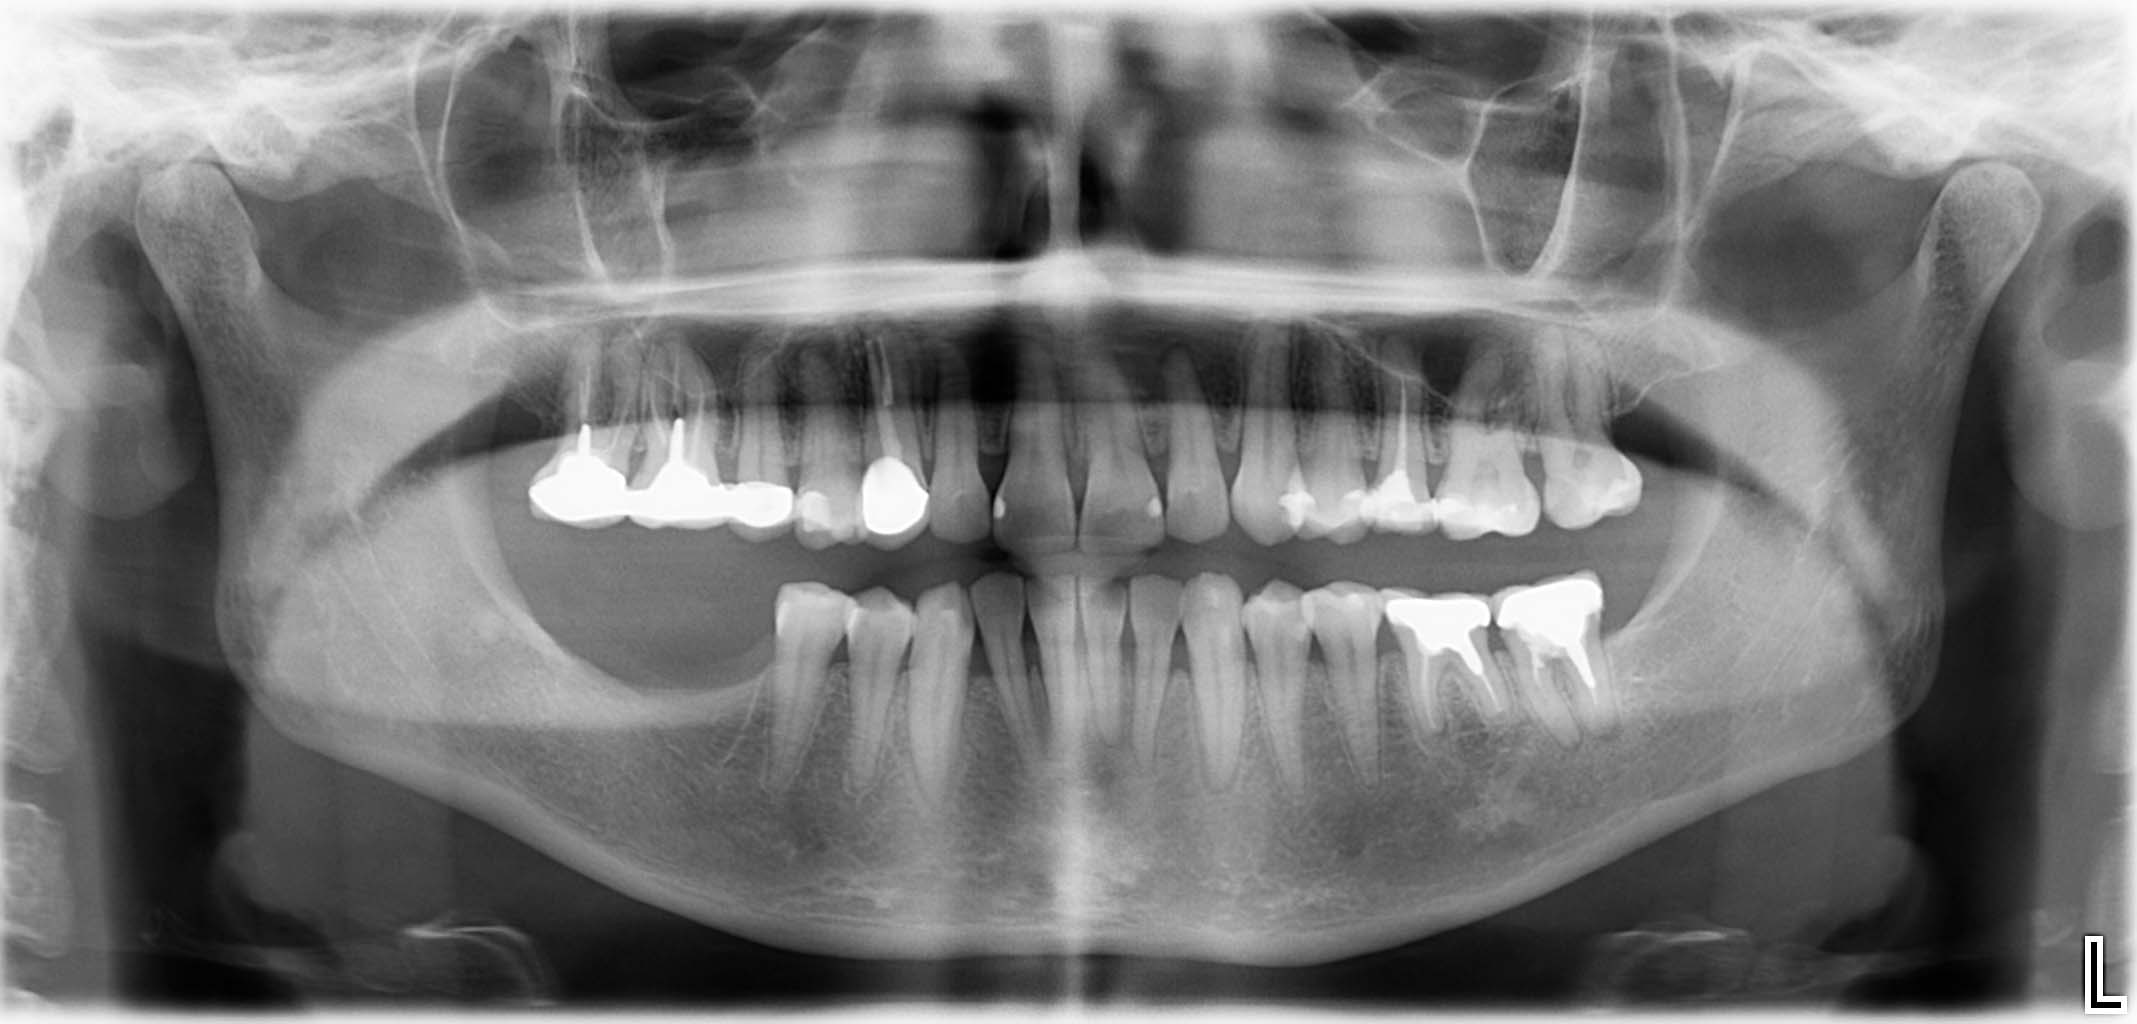

Erfolgreich implantierte Patientenfälle (klinische Fotos)